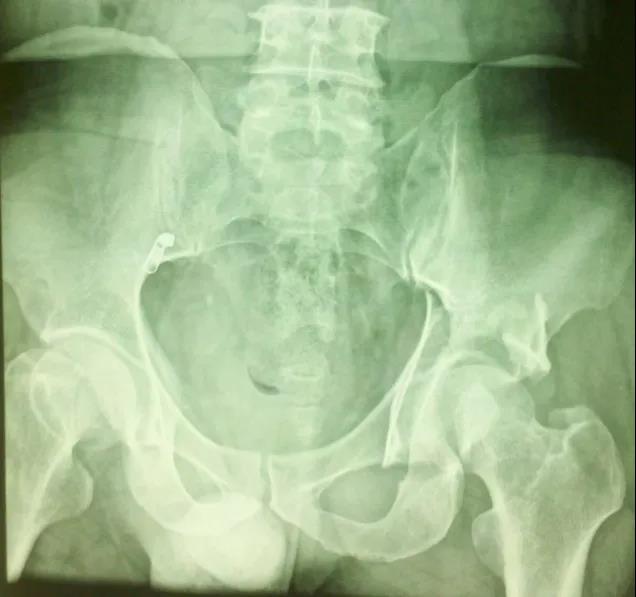

——典型案例——

微创插板病历后路有限切开,结合前路微创插板内